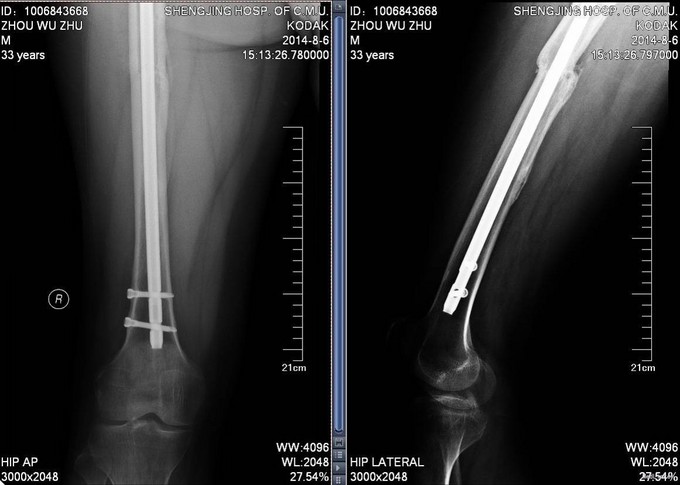

患者2012年8月发生车祸,致右股骨及左胫骨骨折,后于我院行右股骨骨折闭合复位内固定术,左胫骨骨折闭合复位内固定术,手术顺利,安返病房,术后康复锻炼,定期复查,近期复出X线,提示骨折愈合良好,今日门诊以“右股骨骨折,左胫骨骨折术后”为主要诊断收入我科

患者步入病房,神志清,右大腿压痛叩击痛(—),左小腿压痛叩击痛(—)。双下肢等长。双下肢感觉运动均正常。

入院后完善检查,查无手术禁忌症后右股骨干骨折术后内固定物取出术,左胫骨骨折术后内固定物出去术,术后第二天自动退院。